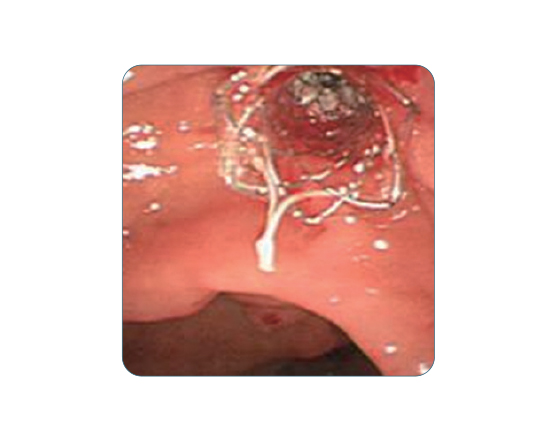

Niti-S Biliary Covered Stent [Bumpy] yüksek performanslı drenaj ve minimal invaziv tedavi ihtiyaçları için geliştirilmiştir. Esnek ve dayanıklı yapısı ile endoskopik prosedürlerde kolay kullanım sağlar.

Hedeflenen alanda etkili drenaj sunar ve migrasyonu önleyici özelliklerle donatılmıştır. Kliniklerde sık tercih edilen bir modeldir.